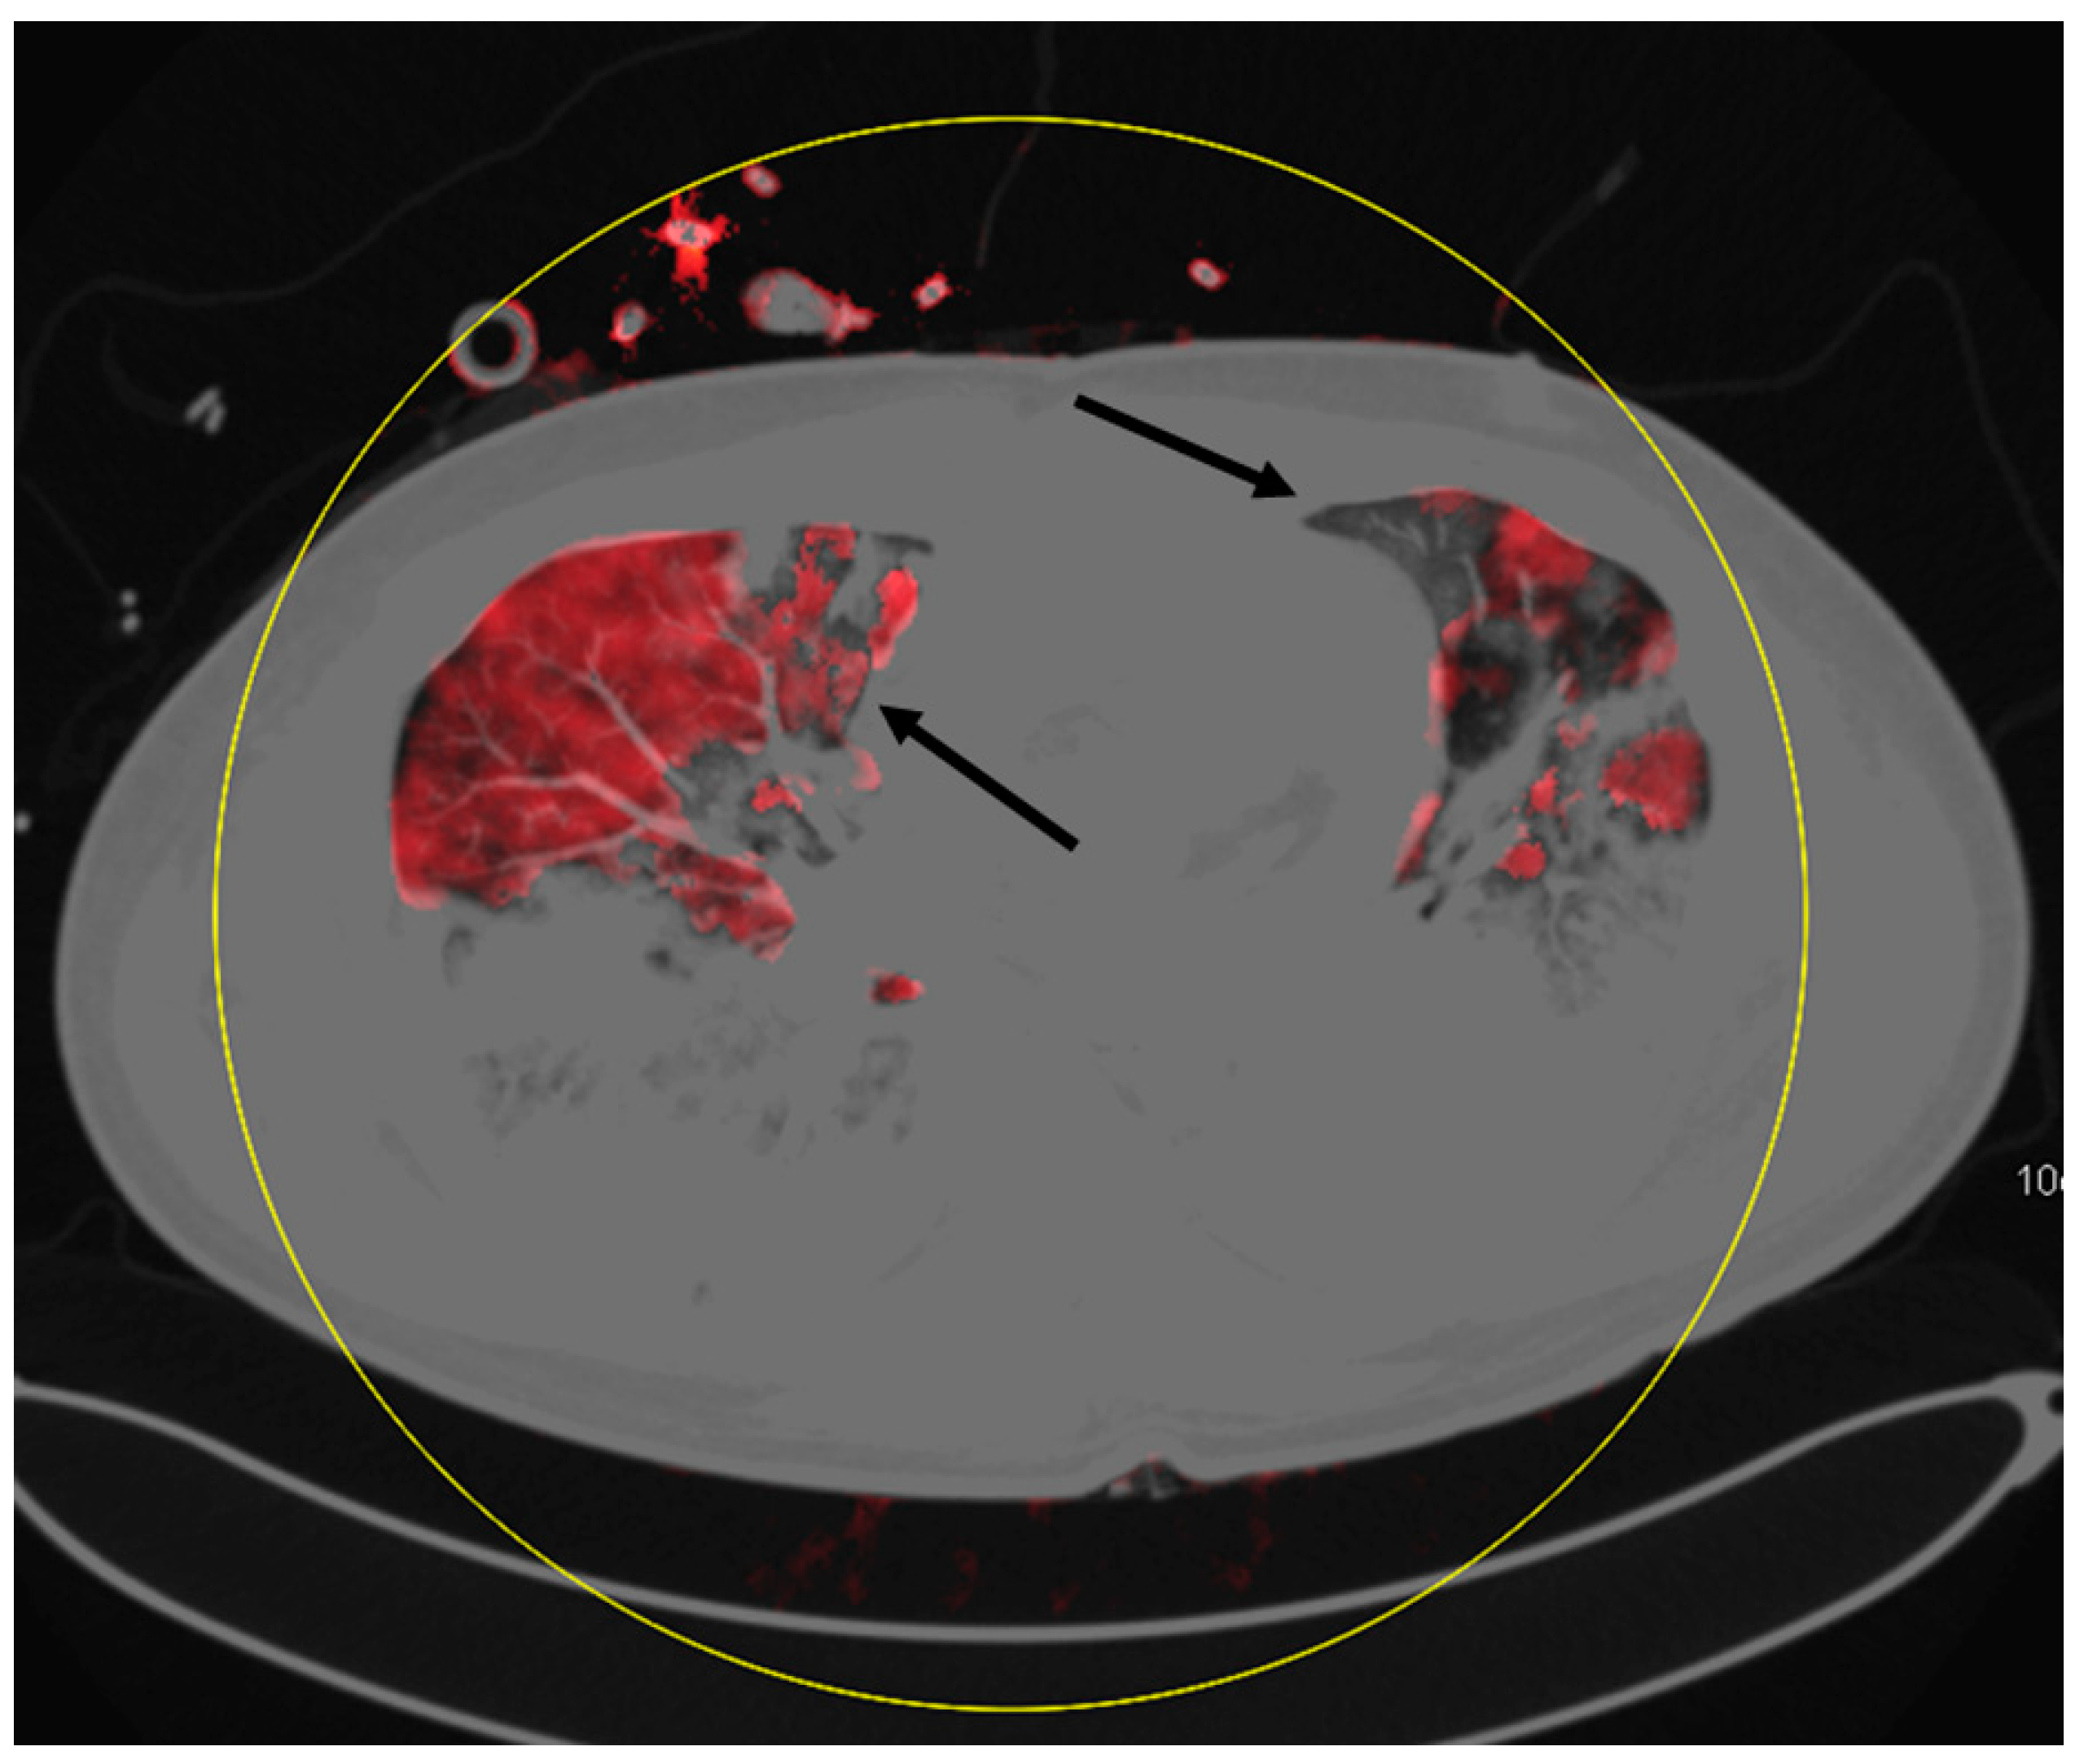

4. Discussion